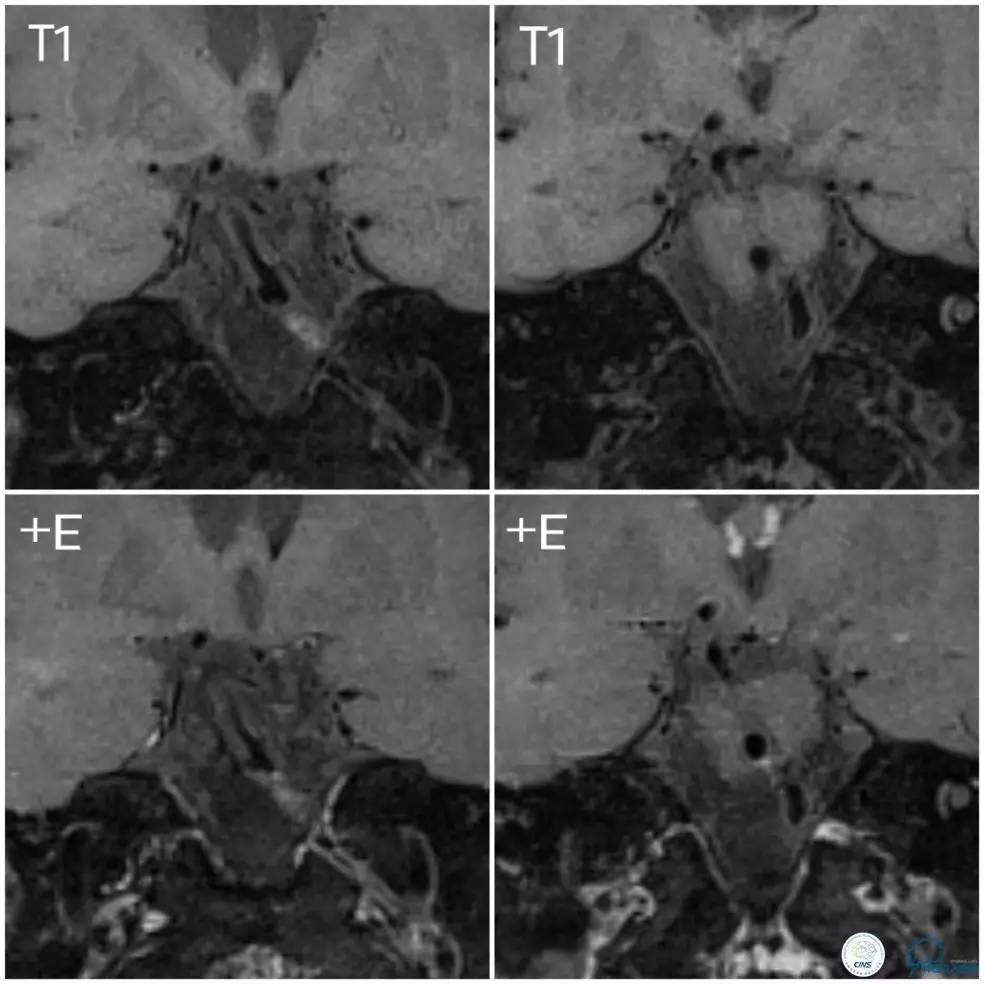

入院后查高分辨核磁:基底动脉局部可见偏心性狭窄,局部可见条状斑块,壁不均匀增厚,管腔内信号增高,注药后可见轻度强化,狭窄远端局部管腔扩张(图3)。右椎V4段略增粗,局部管壁不光滑,可见强化(图4)。左椎动脉显示不清。

图3

图4